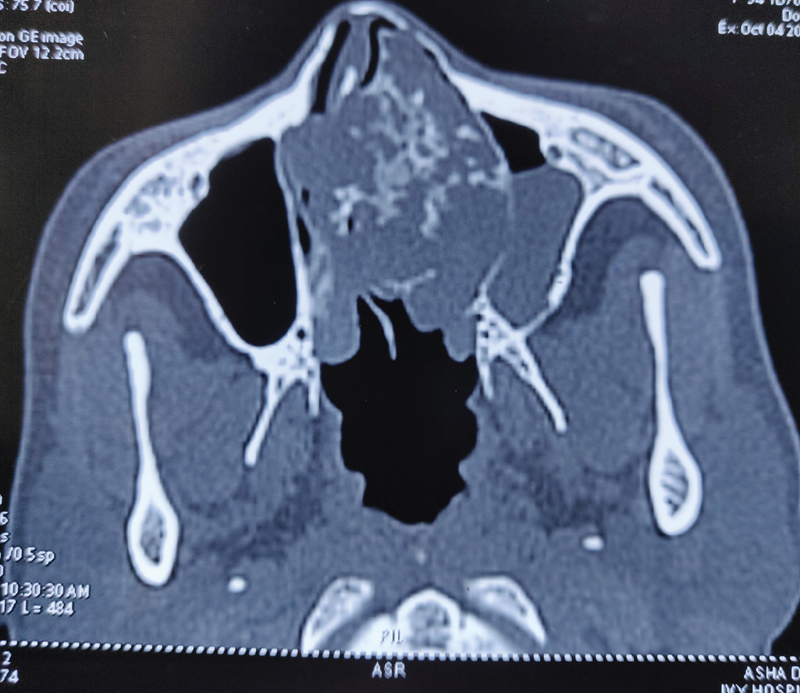

Postop histopathology report was suggestive of grade II chondrosarcoma ([Fig. 2]) with all resection margins free of tumor; the closest margin was 0.2?cm away. In view of clear margins, patient required no adjuvant treatment and was kept on follow-up. Two years post-treatment, the patient is disease free.

|?Fig. 2? Postoperative histopathology.|

Chondrosarcomas are tumors of mesenchymal origin with malignant behavior. The spectrum of these tumors may vary, either low-grade tumors that are indolent to high-grade tumors that are very aggressive. Histopathologically, they are characterized by cellular, poorly differentiated, mesenchymal cells mixed with small areas of well-differentiated cartilage, which looks benign. Grading of the tumors is based on rate of mitosis, cellularity, and nuclear size.[2] Based on these findings, the tumor can be graded into three grades I, II, and III ranging from well differentiated to poorly differentiated tumors. The size and grade of the tumor indicate the local aggressiveness, chances of metastases, and survival outcomes. Grade is the most common prognostic indicator.[7] Our patient had an intermediate grade tumor on the postoperative histopathology. Histological differentials include chondroid differentiation in osteosarcomas, enchondromas, and chondroid chordomas. Immunohistochemical staining is useful for confirmation of chondrosarcomas as they show positive immunoreactivity to cytokeratin and S100 protein.[7]